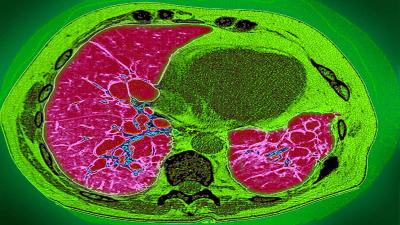

लंग फायब्रोसिस या रोगात फुफ्फुसातील ऊतक म्हणजेच टिश्यू (Tissue) सूजण्यास सुरुवात होते. यामुळे फुफ्फुसांच्या आतल्या हवेची जागा कमी होऊ लागते. याचा परिणाम म्हणजे श्वास घेण्यात अडचण होते. यामुळे एखाद्या व्यक्तीला थकवा जाणवतो. जर परिस्थिती अधिक गंभीर झाली तर रुग्णाचा मृत्यूही होऊ शकतो किंवा त्याला हृदयविकाराचा झटका येऊ शकतो.

याचबरोबर, डॉ. उदवागिया यांनी सांगितले की, काही रुग्णांना बरे झाल्यानंतरही त्यांच्या घरी ऑक्सिजनची आवश्यकता असते. जेव्हा रुग्ण बरे झाल्यानंतर तीन महिन्यांनंतर सीटी स्कॅन केला जातो, तेव्हा त्यांच्या फुफ्फुसांची अवस्था अत्यंत खराब असल्याचे निदर्शनास आले आहे. तीन दशकांपूर्वी लंग फायब्रोसिस रोग सहसा फारच कमी लोकांना होता. ज्यास्तकरून हा रोज वयस्कर लोकांना होता.

फुफ्फुसांची ऊतक सूजलेली आहे. ऑक्सिजनची कमतरता आहे. अशा परिस्थितीत, शरीरात रक्ताचा प्रवाह कमी होऊ लागतो. हृदय योग्यरित्या कार्य करत नाही. याचा परिणाम बहु-अवयव निकामी होणे, हृदयविकाराचा झटका किंवा गंभीर स्थितीत मृत्यू देखील असू शकतो.